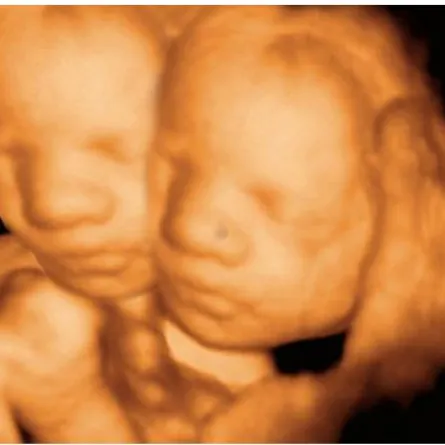

وبعد إجراء التشخيص للعجوز كانت النتيجة غير متوقعة، إذ اكتشف الأطباء أثناء إجراء التصوير بالأشعة وجود جسم غريب في بطن العجوز وليس بداخل رحمها، وبعدها اتضح أنَّه جنين متحجر كامل ظلت تحمله منذ 35 سنة، ووزنه يزيد عن 2 كيلوغرام، ويشبه موميات الفراعنة، وما زاد الأمر غرابة أنَّ الجنين كبر حتى وصل الشهر السابع، وهو كامل الأطراف السفليَّة والعلويَّة، والرأس والبطن، لكنَّه متحجر.

تجدر الإشارة إلى أنَّ حالات «الجنين المتحجر أو المتكلس» تحدث نتيجة لحدوث حمل خارج الرحم، حيث يتطور الجنين خارج رحم الأم، ولا يجد وسيلة لمغادرة جسم الأم، وبدلاً من تعفن الجنين داخل بطن الأم وتعريضها للعدوى المحتملة، يعمل جسدها تلقائياً على تكليس أو تحنيط الجنين في الكالسيوم.